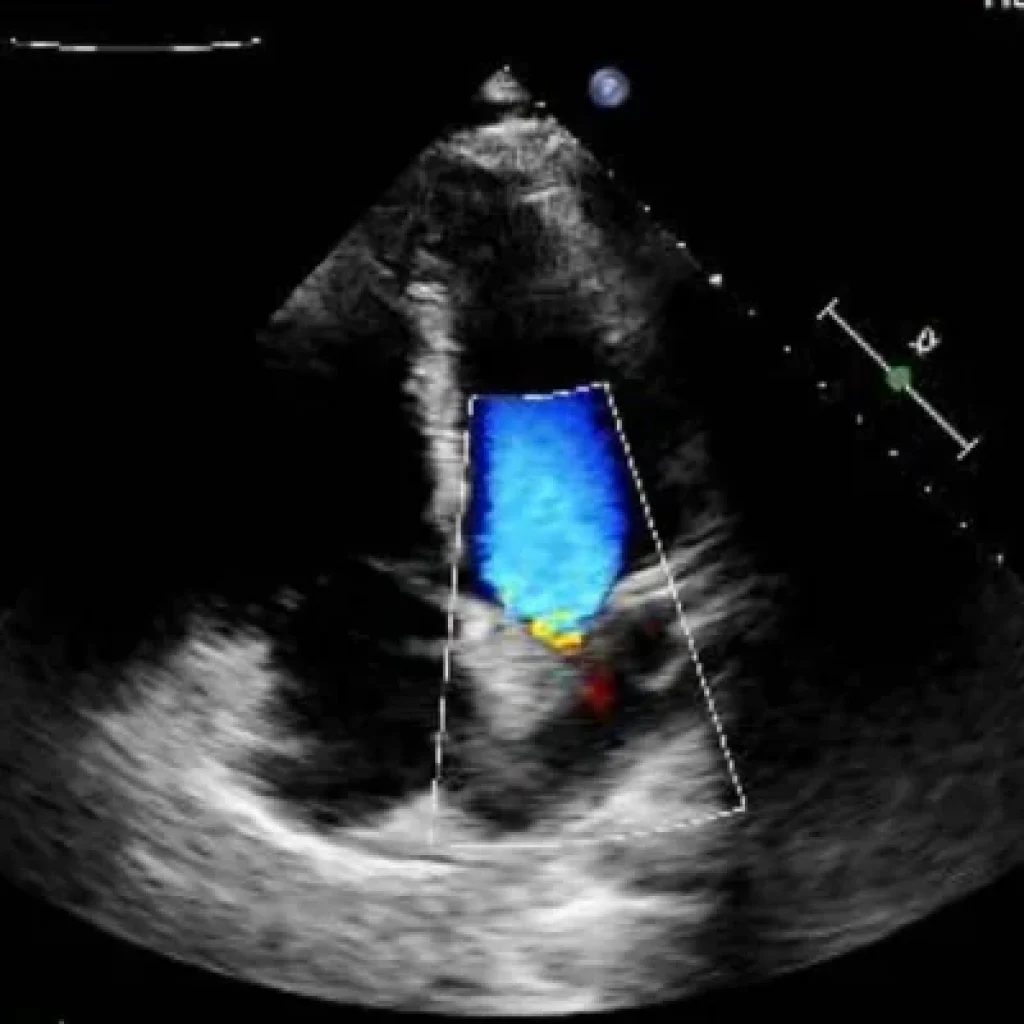

Em uma publicação, o influenciador mostrou exames que mostram a presença da bala no coração, além de imagens do veículo alvejado e da cicatriz no peito e na perna, onde também atingido.